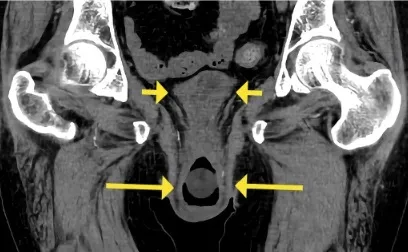

Cómo tratar la fibrilación auricular en la enfermedad renal crónica

Cómo tratar la fibrilación auricular en la enfermedad renal crónica

El paciente con ERC (Enfermedad Renal Crónica) tiene una alta prevalencia de fibrilación auricular. ¡Consulta esta actualización sobre su manejo!